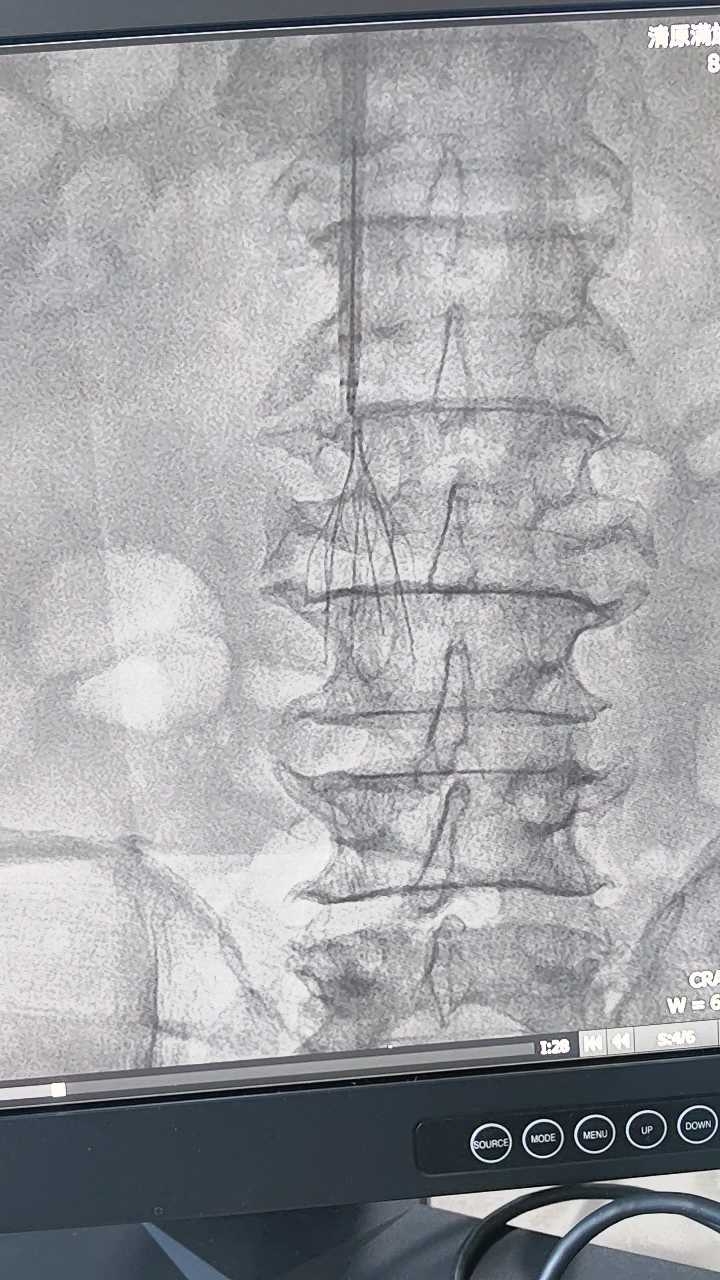

完善术前检查后,患者平卧位,心电监护、吸氧。右侧颈部消毒铺巾,2%卡因局麻后穿刺颈内静脉,植入造影导管。造影示滤器位置正常,无充盈缺损。

。再次造影无外溢,